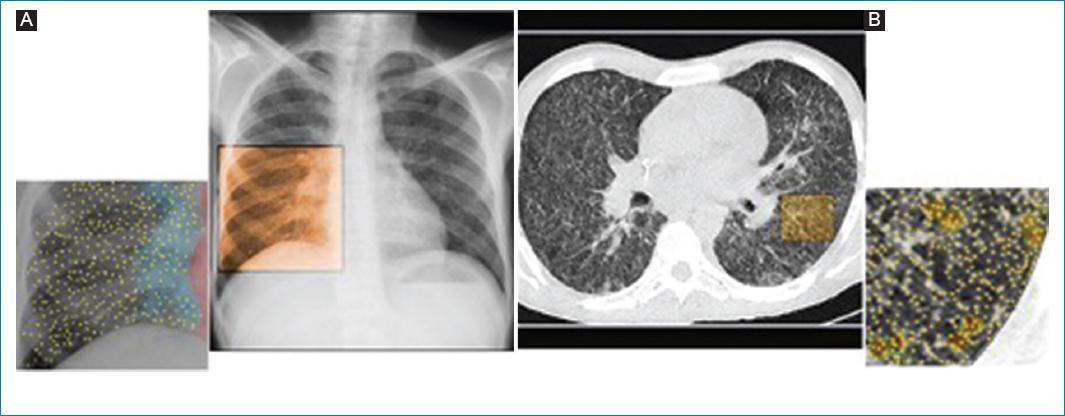

Neuroimagen: realce meningeo basal, hidrocefalia, infartos (vasculitis), tuberculomas